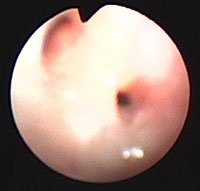

気管支鏡検査:第7病日に行った。肉眼所見で、左右主気管支内に白色円柱状物が多数みられた(図2)。ブラシ擦過細胞診にて、気管支粘膜上皮細胞、好酸球、杯細胞がみられた(図3)。気管支肺胞洗浄液(BAL)[RB2, 10ml×3, 回収率90%]にて総細胞数の軽度増加(421/μl)、好酸球数の増加(26.75%)がみられた。BAL液の培養にて細菌も真菌も検出されなかった。

図2 症例1の気管支鏡検査所見。左右主気管支内に白色円柱状物が多数みられた。